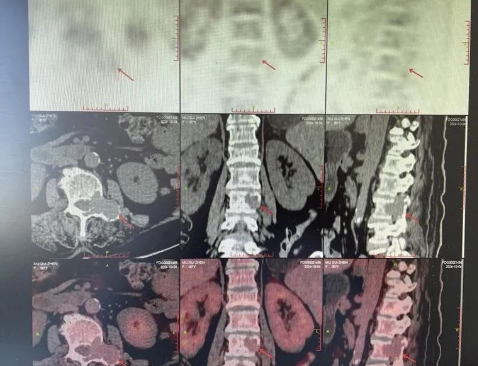

品質(zhì)國(guó)文 | 精準(zhǔn)醫(yī)療 影像先行——西門子New Force雙源CT

采用雙球管+雙探測(cè)器設(shè)計(jì),掃描速度達(dá)0.25秒/圈,1秒完成全身大血管成像,擺脫心跳、呼吸等運(yùn)動(dòng)偽影、金屬植入物偽影的干擾,極大程度減低了控制心率的要求和屏氣的時(shí)間。 閱讀量:1535